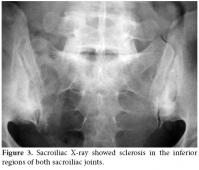

The laboratory testing results were as follows: rheumatoid factor (RF), 11 U/ml (0-20); erythrocyte sedimentation rate (ESR), 67 mm/h (0-20); C-reactive protein (CRP), 85.43 mg/dl (0-5); and the total blood count, urea, creatinine, and electrolyte values were normal. The hepatitis, antinuclear antibody (ANA) along with the Salmonella and Brucella titers were all negative. The purified protein derivative (PPD) skin and pathergy tests were also negative. No findings were detected on the throat culture or in the direct fecal and parasite examinations. HLA-B27 was negative. A chest X-ray showed the hilar plenitude (figure 1). High resolution computed tomography (HRCT) revealed the bilateral hilar lymphadenopathy (LAP) and multiple mediastinal LAP along with several nodules adjacent to several irregular nodules (the largest was 2.5x1.5 cm) in both lungs, which was compatible with stage II sarcoidosis (figure 2). Using a gallium-67 whole body screening method, an activity enhancement in both the hilar and mediastinal regions was consistent with lymph node involvement. The diagnosis of sarcoidosis was confirmed by a bronchoscopic biopsy. A pelvis radiograph and sacroiliac magnetic resonance imaging (MRI) were performed, and the results were normal. The patient was diagnosed as having Löfgren's syndrome, which is a clinical subtype of acute sarcoidosis involving acute arthritis, LAP, and EN. Steroid treatment was administered, and recovery was observed on the arthritis of the right ankle and EN after two weeks. On follow-up, the clinical and laboratory findings (ESR, 35 mm/h; CRP, 7.89 mg/dl) had improved dramatically. During the clinic management of the patient at three months, the patient complained about hip pain, so a radiograph of the sacroiliac joint was performed again. Sclerosis was shown in the inferior regions of both sacroiliac joints on the sacroiliac X-ray (figure 3), and right sacroiliitis was found on the MRI of the sacroiliac joints (figure 4). The complaints of the patient were address by administering nonsteroidal antiinflammatory drugs (NSAIDs), and the patient continued to be followed up.